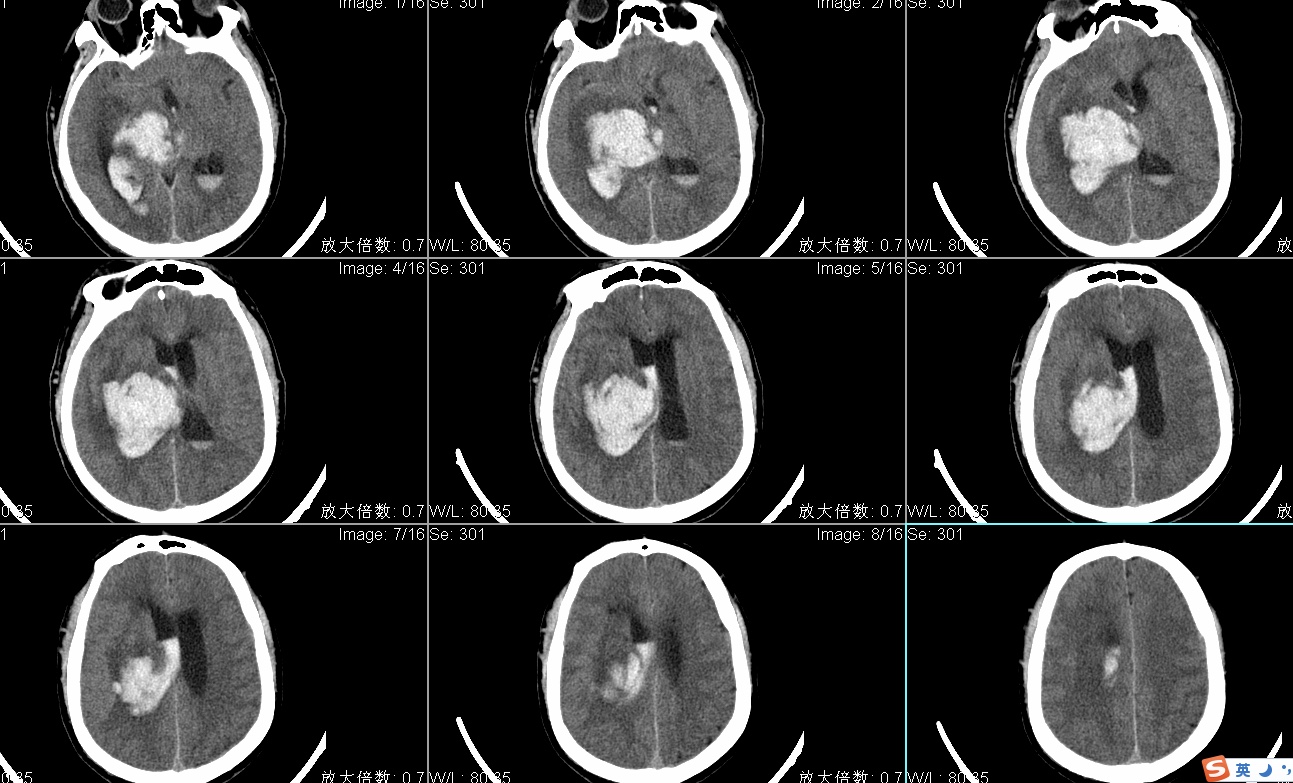

头CT显示右侧丘脑出血破入脑室多田公式计算出血量约50ml;

手术入路:神经内镜辅助右丘脑出血清除术。